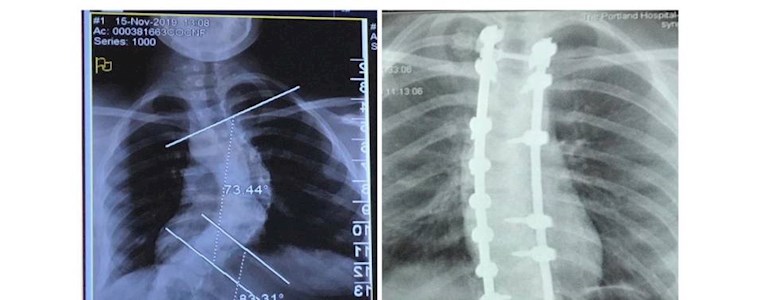

When Hattie first felt her back hurting in March 2019, her parents didn’t think it was anything serious. However, a scan in October that year revealed a significant curvature of Hattie’s spine.

Diagnosing scoliosis, Hattie’s paediatrician referred her for further investigation and a consultation at The Portland Hospital with Mr Lucas.

Hattie’s final morning in hospital started with a much-needed lie in. Then, as Hattie and her family saw her post-operative X-rays, they were overjoyed. “Seeing how straight her spine had become was amazing!” remembers Anna. “Maria helped Hattie with stair-based physio, and gave us some invaluable advice on caring for Hattie at home. I got really emotional and cried when she said goodbye!”